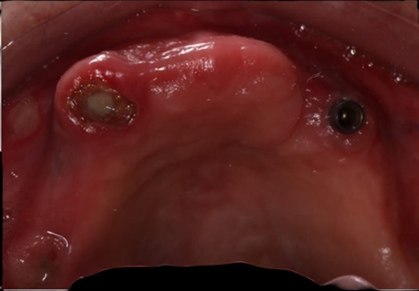

Clinical examination on the upper jaw indicated that she was missing all her teeth, a localized gingival enlargement on the anterior region, an unevenly resorbed upper ridge, an implant with no cover screw, root tip on 13, and an implant head could be seen in the gingiva area of 16 (Figure 1).

Figure 1: Clinical situation of the upper jaw at the initial consultation.

Figure 13: Occlusal view of the maxilla.